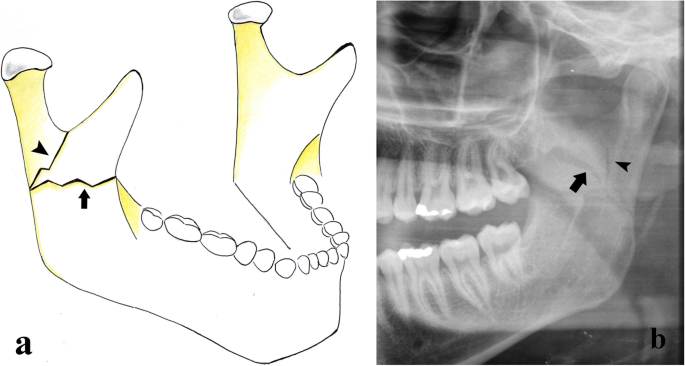

Angle fracture. a Picture showing a vertical fracture that runs distally to the third molar (arrowheads). It is a displaced fracture since the masseter muscle (asterisk) pulls the distal bone fragment upwards and medially. b Cropped panoramic radiograph. Mandibular angle fracture involving an impacted third molar (arrow)

Ramus fractures. a Picture showing that the mandibular ramus fracture can be vertical (arrowhead) or horizontal (arrow), depending on the direction of the fracture rhyme. b Cropped panoramic radiograph. Combined fracture of the left mandibular ramus. The fracture rhyme originates from the external face of the ramus and has both a vertical (arrowhead) and a horizontal (arrow) course